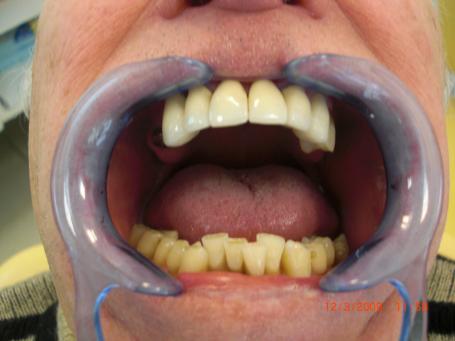

7°) Gencive artificielle en céramique rose

Une fausse gencive en céramique rose est réalisé dans le but de restaurer l’esthétique. Cela évite de faire des dents trop longues pour combler la perte osseuse dû aux précédentes extractions dentaires.

8°) Photo finale